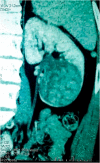

With about 110 cases reported in literature, juxtaglomerular cell tumors are rare. We report a 25 years old patient who was admitted in neurology for a hemorrhagic stroke secondary to a cerebral aneurysm rupture due to high blood pressure. Etiological investigations showed a solid mass of the left kidney. A radical nephrectomy was realized and pathological examination and immunohistochemical profile concluded to juxtaglomerular cell tumor. The originality of this observation is based on the mode of presentation of a rare renal tumor by a malignant high blood pressure.